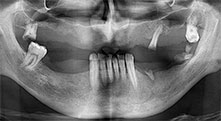

Bratu: We routinely use the instruments for harvesting bone blocks and splitting alveolar ridges. We also use the Piezomed B6/B7 for osteotomy of impacted teeth and removing failed implants. All indications that require deep, clean cuts.

What do you consider the advantages of piezo surgery in relation to oral tissue?

Bratu: I consider piezo surgery a great leap forward in oral surgery. The technique makes bone preparation safer and easier. Little bone is lost, for example in extractions. This is very important in the aesthetic zone, particularly if immediate implantation is planned. Piezo surgery is also safer for soft tissue: injuries to membranes in the sinus are basically history, as are nerve injuries when bone blocks are being harvested. Data indicating reduced postoperative swelling and pain are also available. Piezo surgery is also ideal for preparation of sinus septa. And last but not least, our patients benefit from the atraumatic nature of this technology.